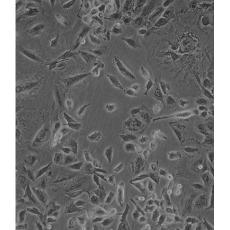

NCI-H1975

產品名稱 NCI-H1975

中文名稱 人肺腺癌細胞

組織來源 肺腺癌;女性

生長特性 adherent

形態特征 epithelial

細胞描述 該細胞是1988年7月從一名女性(無抽煙史)非小細胞肺腺癌組織中分離得到的。

細胞傳代步驟 如果細胞密度達80%-90%,即可進行傳代培養。1. 棄去培養上清,用不含鈣、鎂離子的PBS潤洗細胞1-2次。2. 加2ml消化液(0.25%Trypsin-0.53mM EDTA)于培養瓶中,置于37℃培養箱中消化1-2分鐘,然后在顯微鏡下觀察細胞消化情況,若細胞大部分變圓并脫落,迅速拿回操作臺,輕敲幾下培養瓶后加少量培養基終止消化。3. 按6-8ml/瓶補加培養基,輕輕打勻后吸出,在1000RPM條件下離心4分鐘,棄去上清液,補加1-2mL培養液后吹勻。4. 將細胞懸液按1:2到1:5的比例分到新的含8ml培養基的新皿中或者瓶中

復蘇細胞步驟 將含有1mL細胞懸液的凍存管在37℃水浴中迅速搖晃解凍,加入4mL培養基混合均勻。在1000RPM條件下離心4分鐘,棄去上清液,補加1-2mL培養基后吹勻。然后將所有細胞懸液加入培養瓶中培養過夜(或將細胞懸液加入10cm皿中,加入約8ml培養基,培養過夜)。第二天換液并檢查細胞密度。

細胞凍存步驟 :待細胞生長狀態良好時,可進行細胞凍存。下面T25瓶為例;1.細胞凍存時,棄去培養基后,PBS清洗瓶底1-2次后加入1ml胰酶,細胞變圓脫落后,加入2ml完全培養基終止消化,可使用血球計數板計數。2.1000RPM離心5分鐘去掉上清。用血清重懸浮,加DMSO至最終濃度為10%。加入DMSO后迅速混勻,按每1ml的數量分配到凍存管中,注意凍存管做好標識。本公司按每個凍存管細胞數目大于1X106個細胞凍存。3.將凍存管置于程序降溫盒中,放入-80度冰箱,至少2個小時以后轉入液氮灌儲存。記錄凍存管位置以便下次拿取。

細胞凍存 Freeze medium: 50% basal medium+40% FBS+10%.DMSOStorage temperature: liquid nitrogen vapor phase

細胞運輸 干冰運輸(2ml凍存管)或活細胞運輸(T25細胞瓶)